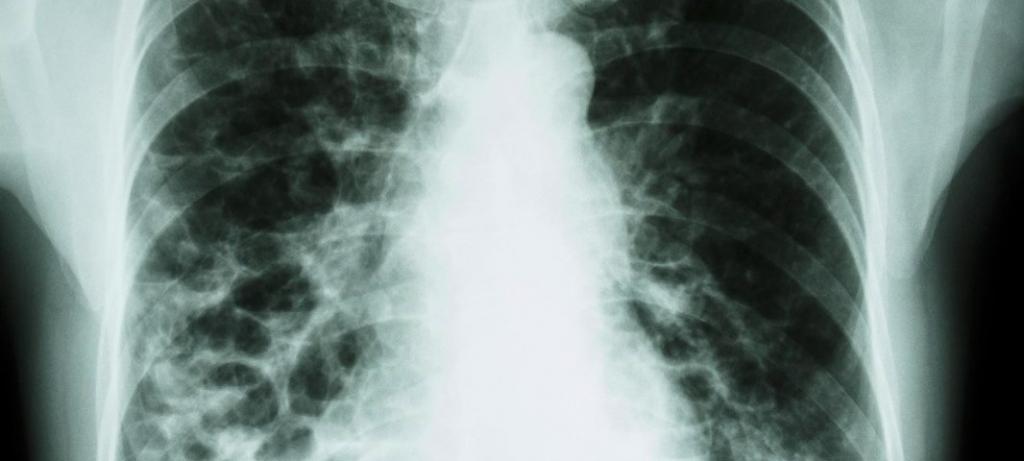

Le principal moyen moderne de détecter la tuberculose est un examen fluorographique. Cette forme de diagnostic est devenue si répandue depuis longtemps et, au cours de cette période, de nombreuses vies humaines ont été sauvées, car la reconnaissance précoce d'une maladie aussi dangereuse que la tuberculose et le démarrage rapide de son traitement sont très importants pour un résultat positif.

Le principal moyen de détecter la tuberculose chez les personnes de 15 ans et plus est la fluorographie, dont les résultats peuvent être obtenus presque instantanément. En cas d'écart par rapport à la norme, une analyse de sang est ensuite prescrite à la personne. Il est ensuite recommandé de répéter l'étude.